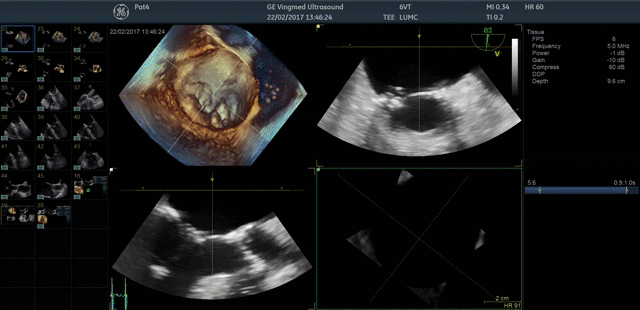

Ultra-high single-beat volume rates With TEE procedures growing, so is the need to find ways to achieve the benefits of 4D imaging without compromising productivity. VmaxTM enabled by cSound™ 2.0 offers ultra-high 4D volume rates acquired in single beat acquisition with no loss of image quality. Elimination of ECG gated multibeat/stitching acquisition provides enhanced overview of structures and function in cases with high and/or irregular heart rhythm - which potentially reduces interventional procedure time and improves patient outcomes.

4D TEE color imaging with Vmax